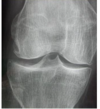

Que alteração degenerativa da osteoartrite é evidenciada nessa imagem?

Esclerose óssea subcondral

Quais os achados degenerativos que podem ser encontrados na imagem da osteoartrite?

Redução do espaço articular

Osteófitos

Esclerose óssea subcondral